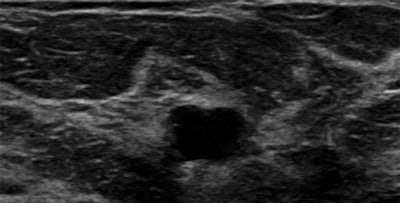

Images are of a 69-year-old postmenopausal woman who had mammographic screening. Screening mammograms (left craniocaudal and left mediolateral oblique views, respectively) show a mass with ill-defined margins in the posterior third of the left breast at 1 o'clock position. All images courtesy of RSNA. B-mode ultrasound scan shows hypoechoic mass with ill-defined margins in left breast at 1 o'clock position.

B-mode ultrasound scan shows hypoechoic mass with ill-defined margins in left breast at 1 o'clock position. T2-weighted turbo spin-echo MR image and magnification view (left) show a round mass as the correlate of the mammographic finding at 1 o'clock in the left breast. The mass is isointense with discrete internal septations. Subtracted T1-weighted gradient-echo MR image (right) obtained after administration of contrast shows no enhancement of the lesion. Ultrasound-guided core needle biopsy was performed, and histologic examination showed a sclerosed fibroadenoma.